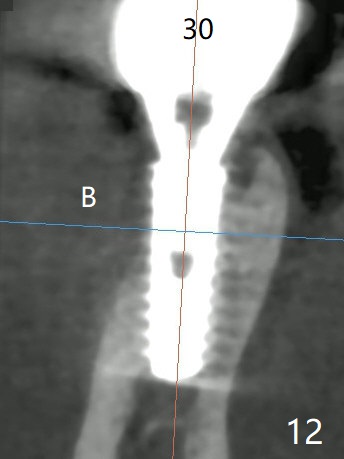

The tooth #29 has mild persistent pain radiating to the temple with mild percussion and mobility I 4.5 months post apicoectomy; the buccal recession is noticeable (Fig.1). Granulation tissue and bone graft are attached to the resected apex of the extracted tooth (Fig.2 <). The initial osteotomy with 1.5 mm drill is distal (Fig.3). After position adjustment with difficulty because of hard bone, osteotomy is finished with 2.8 and 3.2 mm Magic Drills (Fig.4). Following final drill, a 3.5x11 mm IBS implant is placed with insertion torque of 45 Ncm. With placement of a 4.5x4(4) mm abutment, Vanilla graft is placed in the buccal gap (Fig.5). Immediately postop CT shows that the implant is buccally placed (Fig.6,7 B). In fact after extraction (Fig.8), the initial osteotomy should start obliquely and as coronal and lingual as possible (Fig.9 red line). Following the initial penetration, the osteotomy should be straightened (Fig.10) so that the implant could be placed lingually (Fig11 green) to reduce buccal thread exposure. In fact there is also buccal thread exposure at #30 (Fig.12). The bone loss at #29 and 30 is minimal 4 months postop (#29, Fig.13 *)) and severe with periimplantitis at #29 one year post cementation (Fig.14). Incision will be made to exposure buccal threads of #29 and 30. If threads are within bone boundary, bone graft will be done with sticky bone after Titanium brush. If not, remove implant threads and bone graft. The worst scenario will be handled with implant removal (trephine bur 4/5 mm), either with bone graft or implant being placed lingually (IBS 3x11 mm 2-piece, to be buried, if needed (Fig.15)). Take preop photos to show #29 and 30 buccal recession and gingival erythema.